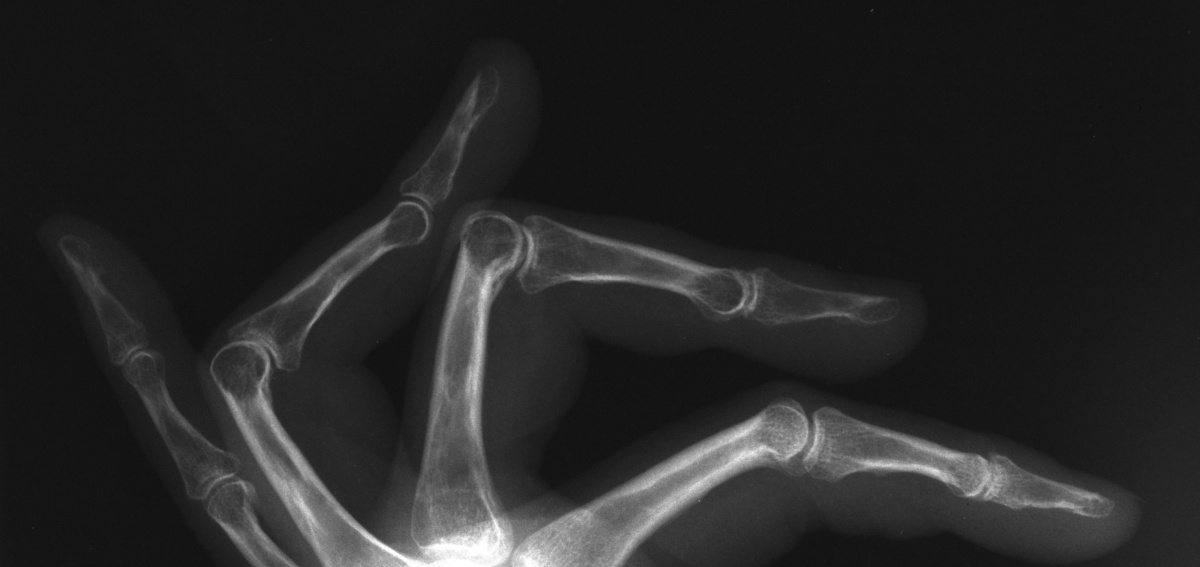

Lateral view shows PIP joint space narrowing, more pronounced in the ring finger. They also show periarticular osteoporosis of the middle and ring fingers compared to  the index and small - impressive in that this is four years post injury and the patient uses the fingers normally within the constraints imposed by contractures.